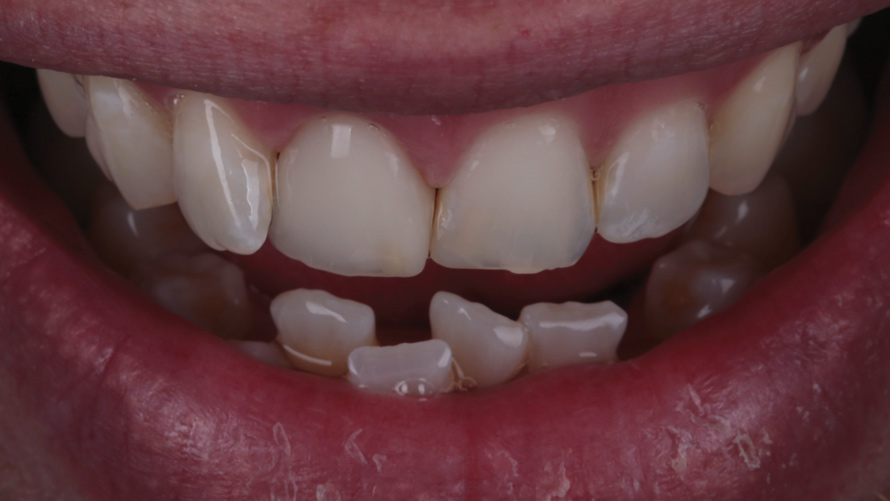

Eight weeks after the initial start of the walking bleach procedure, the final layered lithium disilicate crown was tried-in and evaluated for function and esthetics. Upon patient approval, the intaglio surface of the crown was etched for 20 seconds with a 9.6% hydrofluoric acid etchant, rinsed, and then scrubbed with a 37.5% orthophosphoric acid solution to clean out any ceramic debris. The crown was then placed into an ultrasonic bath of 91% isopropyl alcohol for 5 minutes, after which the intaglio surface was coated with silane and placed under a warm air dryer for 1 minute. A translucent self-adhesive resin cement was used to bond the final restoration to the preparation. The patients both stated that they approved of the form, function, and esthetics of the definitive restoration and that they were very pleased with the final results (Figure 13 through Figure 18). Routine periodic evaluations and radiographs were scheduled to monitor their oral health and esthetics.

(17.) Case 2: Right- and left-side retracted profile views of the definitive all-ceramic restoration on the maxillary left central incisor.

Figure 17

(1818.) Case 2: Right- and left-side retracted profile views of the definitive all-ceramic restoration on the maxillary left central incisor.

Figure 18